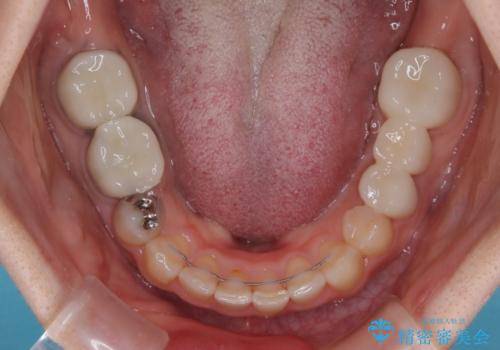

抜歯したスペースがなかなか閉じず、治療に時間はかかりましたが、術前術後のむし歯治療と合わせて3年10ヶ月で治療を終えることができました。

途中結婚により遠方に引っ越しをされたため、むし歯治療は取り急ぎ目立つところをセラミッククラウンとしましたが、今後落ち着いてきたら他の部分も行っていく予定です。